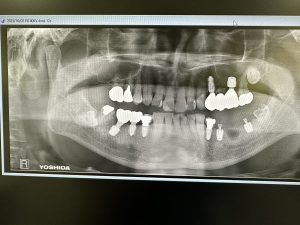

本日は午前、午後とインプラントオペあり

お二方共に浅草橋時代からの患者さん🙏